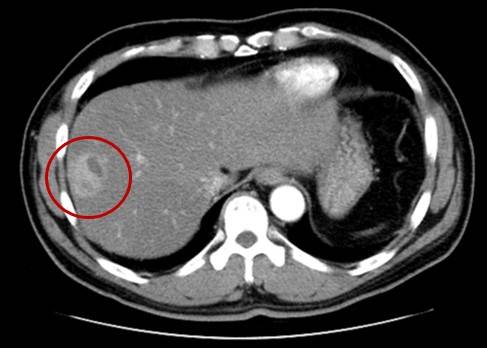

암 치료 기술의 발전으로 간암의 5년 생존율은 39.3%까지 높아졌다. 그러나 여전히 다른 암종에 비해 치료 성적이 낮은 편이다. 간암은 주로 만성 간질환의 결과로 발생하는데, 간암을 치료하더라도 만성 간질환이 치료되는 것은 아니라 재발률이 높기 때문이다. 간경변증으로 간이 이미 많이 나빠진 상태에서는 치료 선택지가 제한되다보니 치료 효과가 떨어질 수밖에 없다. 따라서 B형, C형간염이나 간경변증을 진단받은 40세 이상 고위험군은 국가암검진 프로그램을 통해 6개월마다 간 초음파검사와 혈액검사(혈청알파태아단백 검사)를 받아야 한다. 간경변증이나 지방간이 심해 초음파 영상만으로 간암을 발견하기 어려운 경우 컴퓨터단층촬영(CT)이나 자기공명영상(MRI)이 필요하다. 전문의의 처방에 따라 항바이러스제를 복용할 수도 있다. 현재 C형간염은 항바이러스제를 투약하면 완치가 가능하다. 간염 환자라도 정기 검진을 받고 올바른 생활습관을 갖는다면 간암 발생 위험을 낮출 수 있다.